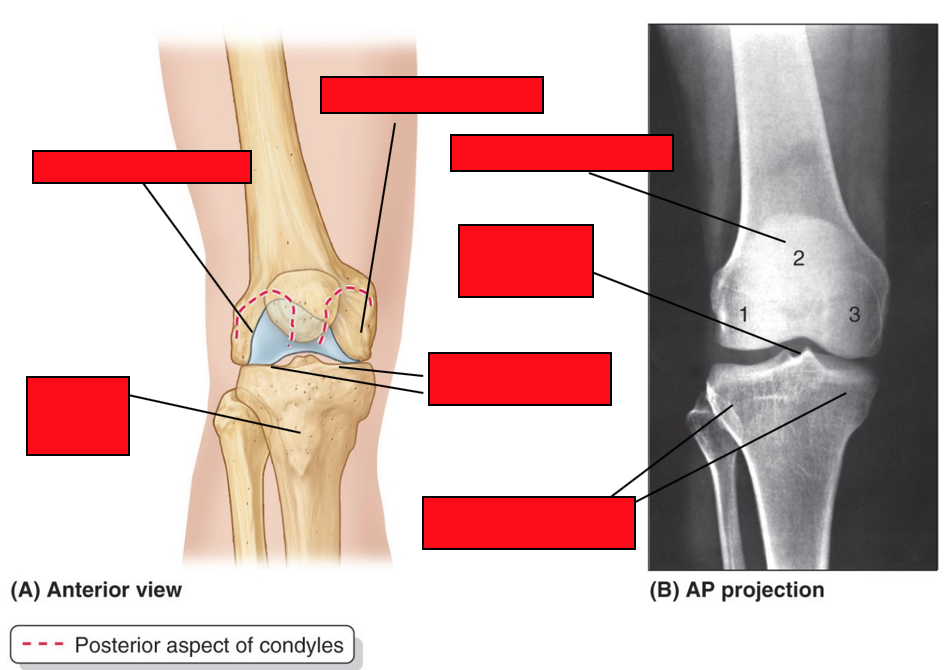

Label the components of the knee joint